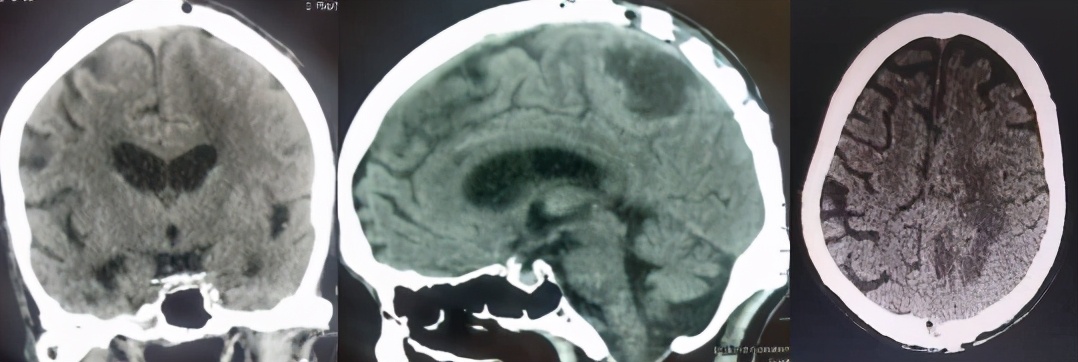

术前CT增强扫描影像(肿瘤位于大脑镰,累及矢状窦)

入院后完善检查,行头颅CT增强检查可见肿瘤位于左侧大脑镰部,并累及上矢状窦,且肿瘤深部还有一囊性病变,肿瘤强化明显,压迫运动区脑组织,造成患者右侧肢体瘫痪。患者年龄大,心肺功能不正常,并合并股骨颈骨折。为了保证手术的顺利进行,外科张强主任组织神经外科、麻醉科、心病科、肺病科、骨科等相关科室,进行会诊和术前讨论,制定了合理稳妥的手术治疗方案。

手术后CT影像(肿瘤已经切除)